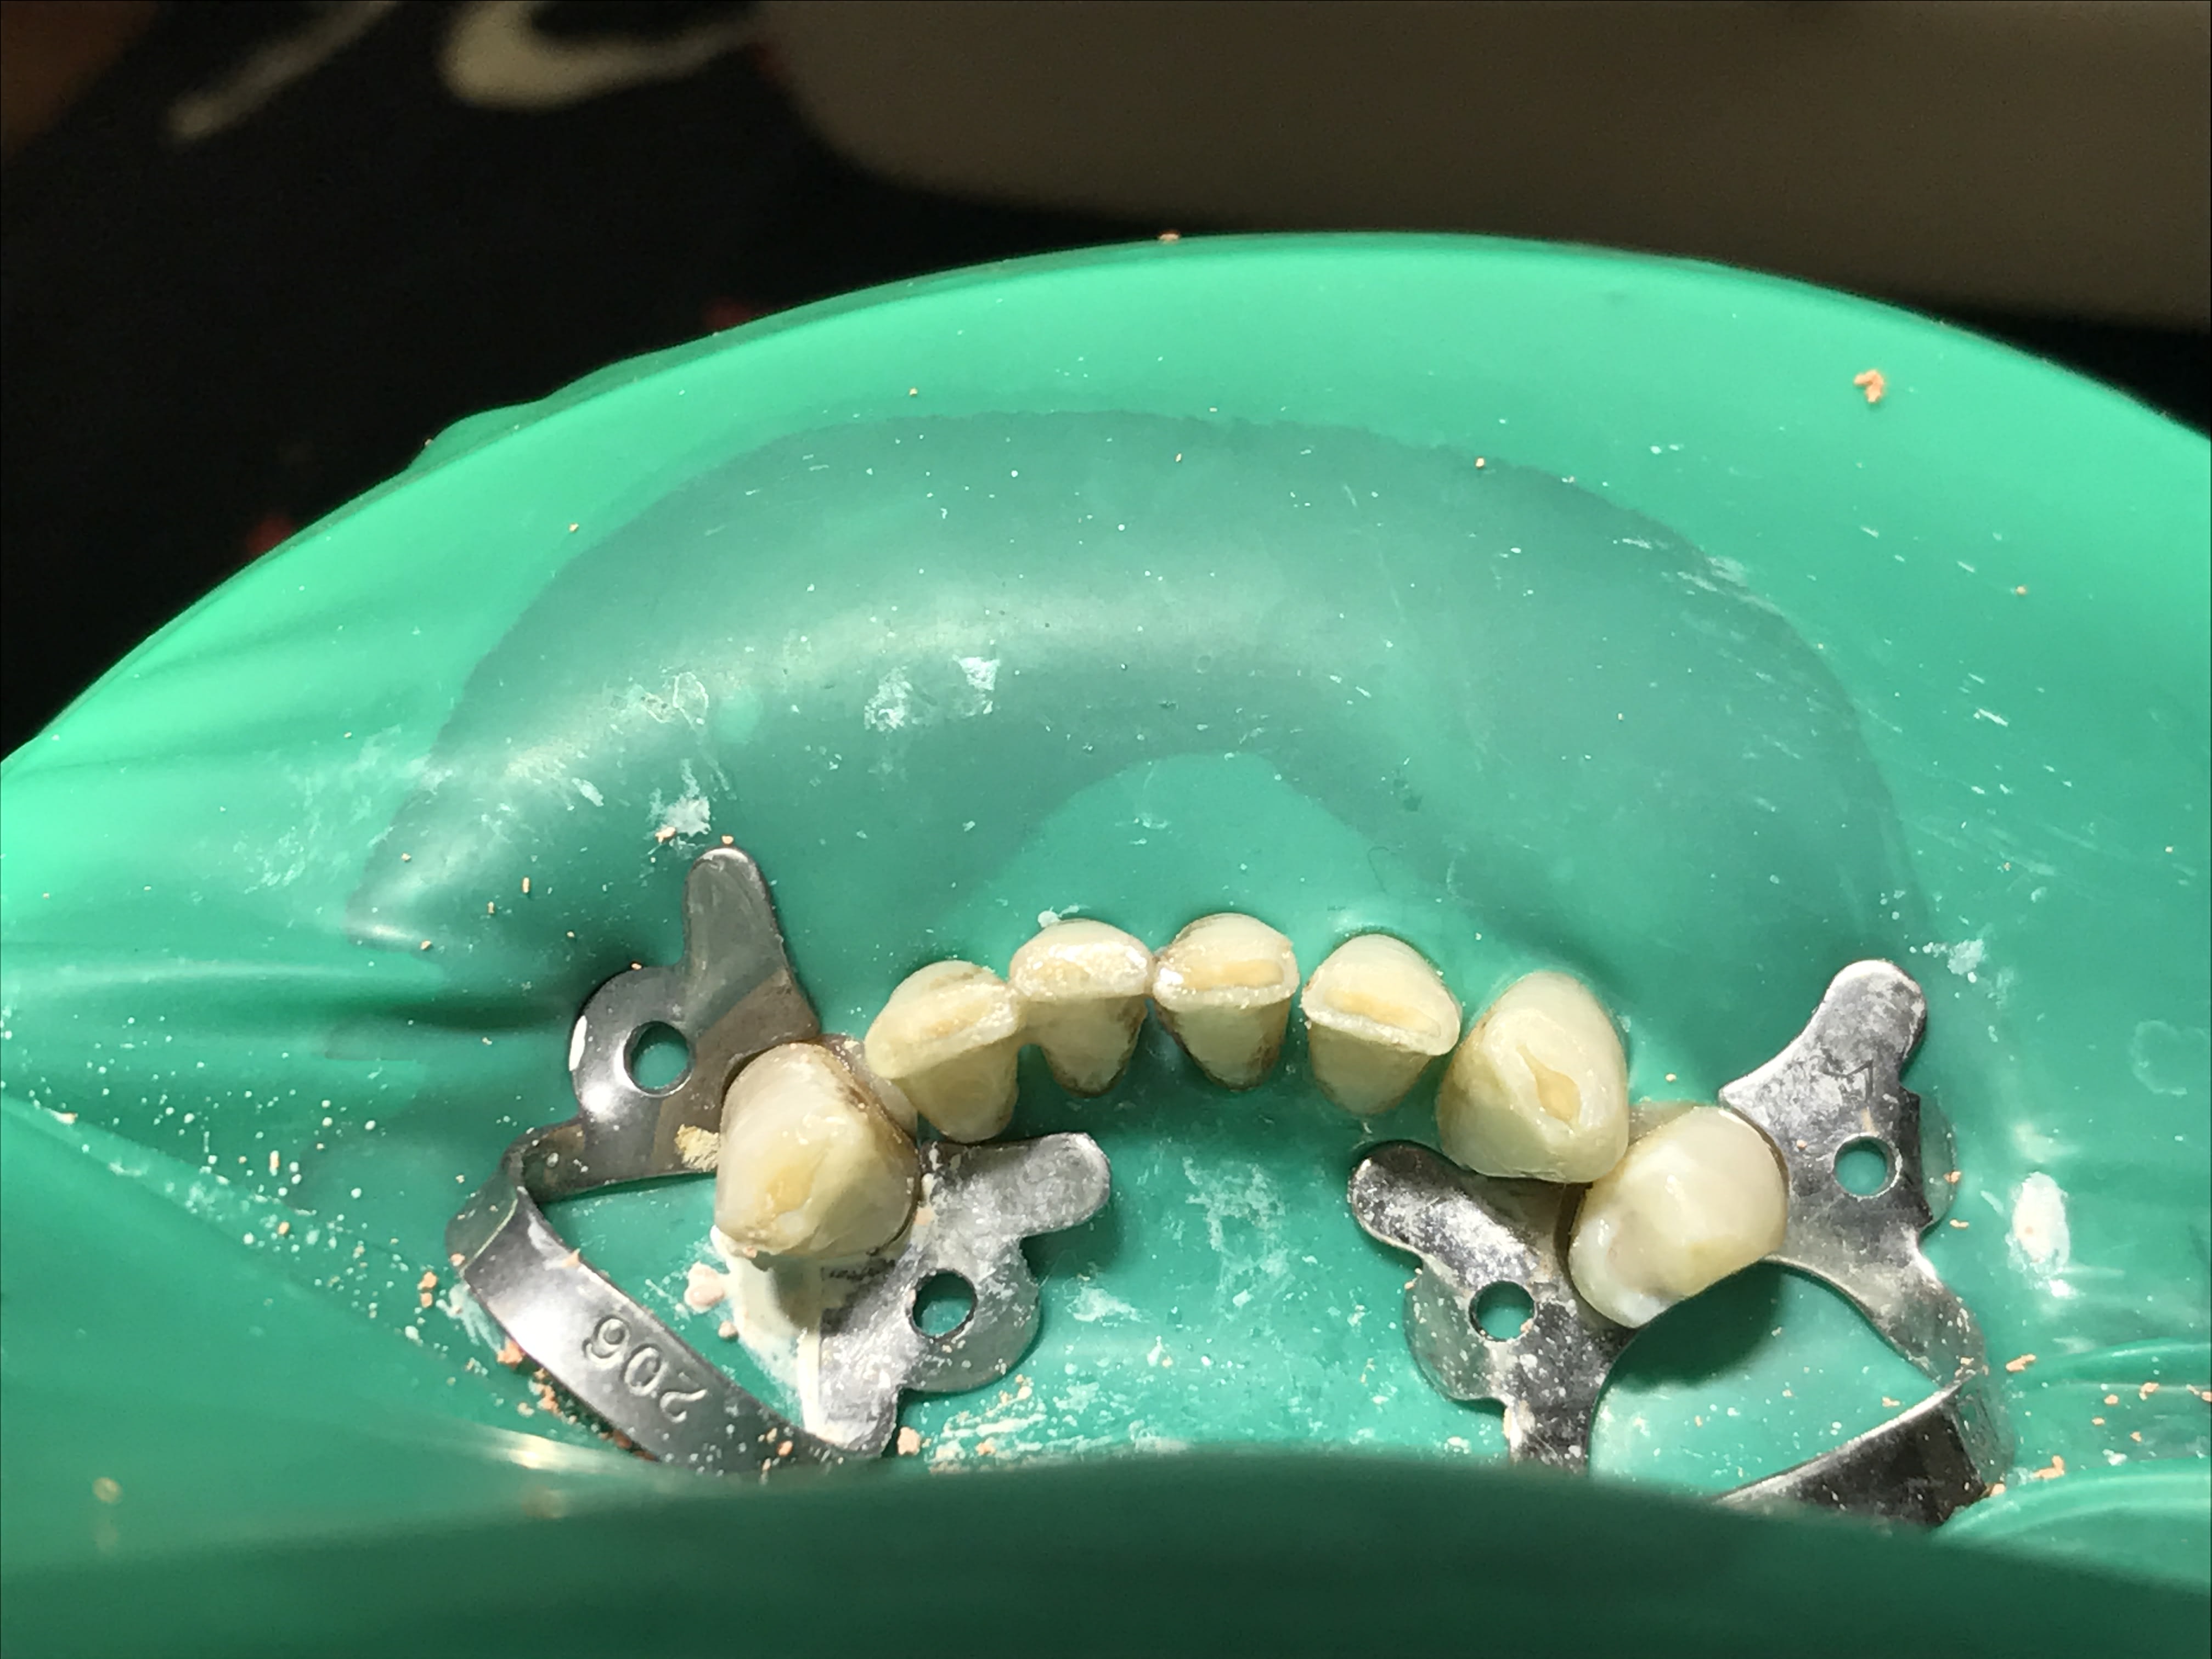

Bon et bien le haut maintenant...

Img 1606 y7zgvi - Eugenol

Img 1610 lptn89 - Eugenol

Img 1615 rpdoqy - Eugenol

Img 1653 obrh1p - Eugenol

Img 1613 ytxave - Eugenol

bon , pour en revenir au sujet, Yiaudat, tu te fais pas chier à faire des RTE...vu l 'état paro en haut c'est direct le sto pour tout ratiboiser, puis des jolies boulettes de compo en bas (pas de signes cliniques...vas pas t emmerder !!!) t as les photos et les radios...

et zou, complet haut/ stellite bas chinois, turc, malgache...